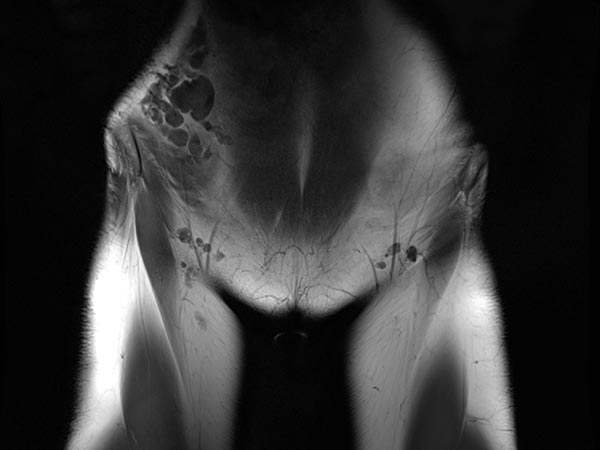

Coronal, T2-weighted, fat-suppressed MRI of the lower abdomen at the level of the groin. Normal inguinal lymph nodes. The lymphatic malformation of the abdominal wall presents as large, dysplastic, balloon-like, septated cysts that are grossly hyperintense (white).